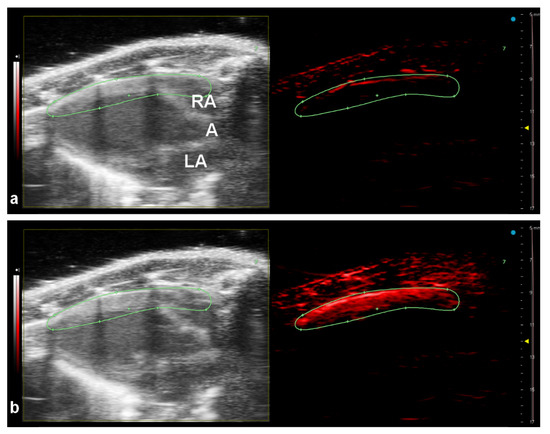

3.4. In Vivo Imaging